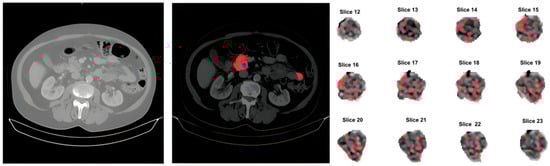

Figure 1.

Processing pipeline. Illustration of the original study (left image), output of the soft-tissue normalization and manual segmentation of the pancreas and lesions, red and blue respectively (middle image) and image feature extraction of the segmented lesion (right image).